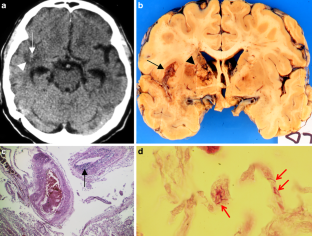

The CNS TB can be manifested (1) diffuse as tuberculous meningitis (TBM), (2) localized as tuberculoma or (3) tuberculous abscess or (4) in extradural and intradural spinal infections. Information on clinical presentation, underlying pathology and the distinguishing features is demonstrated. The TBM is further described, which may lead to cranial nerve palsy, hydrocephalus and infarction due to associated arteritis of the basal perforators. The differential diagnoses are vast and include other infections, such as bacterial, viral or fungal meningoencephalitis, malignant causes or systemic inflammation with CNS. Complicating factors of diagnosis and treatment are HIV coinfection, multi-drug resistance and TB-associated immune reconstitution inflammatory syndrome (IRIS).